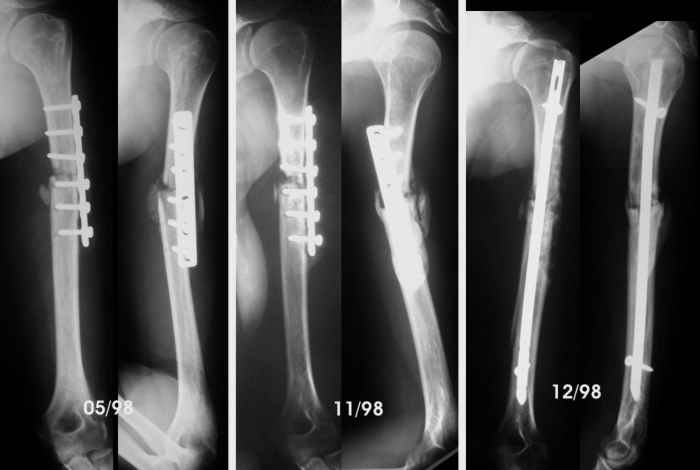

She was close to a tractor power take-off and her clothes caught her. She was pulled towards the tractor and suffered several rib fractures and this humeral fracture (AO-OTA 12-B2). No radial paralysis. She was fixed with Hackettal elastic nailing.

Six months later there was no signs of healing so she accepted to revise the fracture. We used compression plating and autologous iliac bone grafting on April 98.

By the end of May, she complained of sudden pain during physiotherapy, and came with the bottom left x-Ray. We advised to revise the operation, but she wanted to wait in a brace, but by November the humerus hadn't healed so we advised to remove the plate, add more bone graft and nail it. Which we did.

The patient regained full motion and used the arm almost freely till now. She has been working as waitress, postman... although the x-ray never showed healing. She has never wanted to be operated again because the limb was almost pain free.